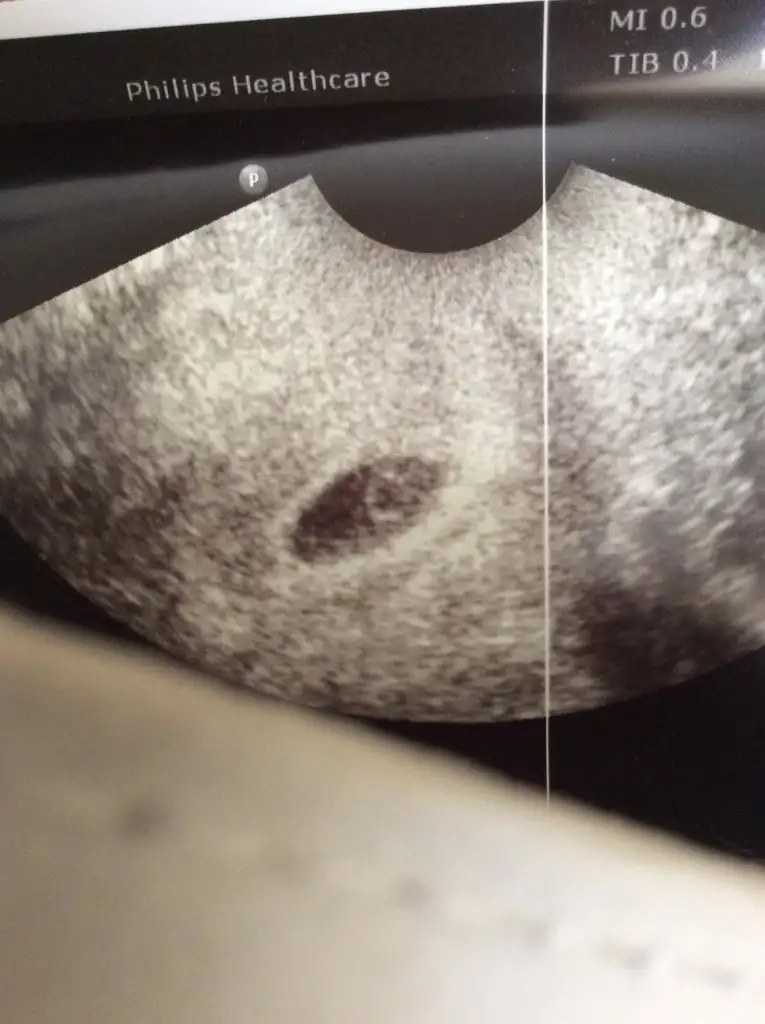

Çok şükür keseyi de içindeki halkayı da gördük, kalp için erken dedi 2 hafta sonra kesin olur stres olmasın 24 Eylül’de gel şu an her şey çok güzel dedi. O kadar mutluyum ki anlatamam. Hepinize desteğiniz için teşekkürler. Bu güzel haberi kutlamaya kahvaltıya gittik tabi 😋 ama bende zerre iştah yok yumurta domates salatalık zor yedim